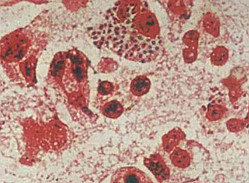

皮肤黏膜念珠菌病常见组织出现红肿、糜烂、溃疡等病变;内脏念珠菌病则有脏器出现脓肿性或肉芽肿病变。脓肿内可见芽孢和菌丝。

3.组织病理

怀疑有念珠菌食管炎的患者,则不仅应做内镜刷取标本检查,同时应做活检,以进一步从组织病理学查找念珠菌侵袭黏膜的证据。 深部念珠菌的组织反应不具特征性。一般呈急性化脓或坏死,可有多个脓肿或微小脓肿,内含大量中性粒细胞、假菌丝和芽胞。组织中的假菌丝和芽胞是深部念珠菌病的确诊证据。

采集病变部位标本以10%KOH制片或革兰氏染色,镜下观察,见有大量的球状出芽酵母菌型和假菌丝,为特征性发现。